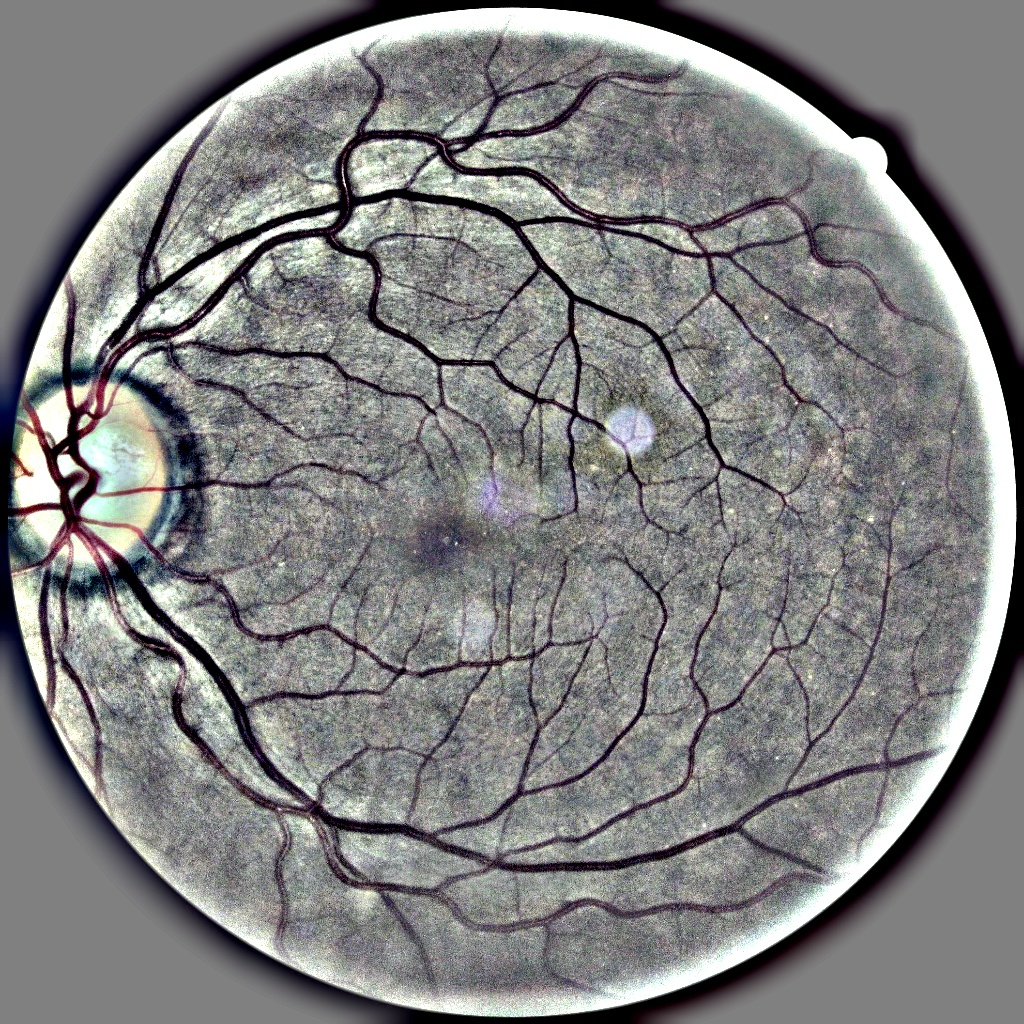

Figure 1 illustrates complete pipeline of the system combining coarse-grained and find-grained classifiers. Before feeding an image to the network, we first applied Otsu Thresholding to extract and crop retinal rim from RFI and get rid of irrelevant black background. Since the images in both datasets are taken with different cameras and under different clinical settings, they suffer from large brightness and color variations. We used adaptive histogram equalization to normalize brightness and enhance the contrast of visual artefacts which are critical for DR detection. Since the images are in RGB colour space, we first translate them into YCbCr colour space to distribute all luminosity information in Y channel and colour information in Cb and Cr channels. Adaptive histogram equalization is then applied on Y channel only and the resultant image is converted back to RGB colour space. We further normalized the images by subtracting local average colour from each pixel to highlight the foreground and help our network detect small features. Figure 1 shows the effects of preprocessing steps on RFIs. These pre-processed images are then used to train all five networks individually. During inference, each network gives diagnosis which are ensembled to calculate the final prediction.

Refer to caption

(a) (a) Original Image before Preprocessing

(b) (b) After Contrast Enhancement

(c) (c) After Local Average Colour Subtraction

Figure 1: Effects of preprocessing steps on retinal fundus images